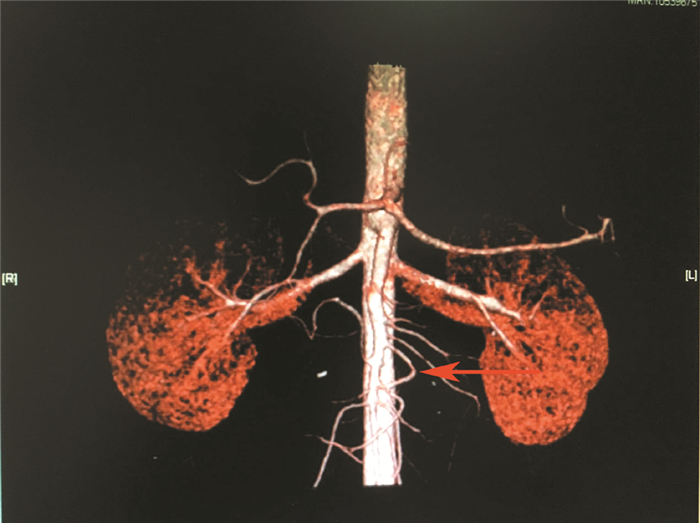

二、实验室及辅助检查血常规、尿常规、粪常规及潜血试验、肝肾功能、电解质、血脂、血糖均无异常。PPD皮试、结核感染T细胞斑点检测以及结核抗体均为阴性。胸部正侧位、腰椎正侧位、腹部立卧位X线检查,肝胆胰脾及泌尿系B超未见异常。上腹部CT加CT血管造影(CTA)示空肠部分旋转至右侧腹,肠曲形态未见异常,肠壁未见水肿;肠系膜上动脉、上静脉分支右旋至右侧腹,旋转角约180°,考虑先天性小肠旋转不良可能性大,见图 1、2。胃镜示慢性非萎缩性胃炎,肠镜示直肠炎症改变。

图 1 一例成人先天性小肠旋转不良上腹CTA 箭头所示为肠系膜上血管分支右旋 |

图 2 一例成人先天性小肠旋转不良CTA三维重建 箭头所示为肠系膜上动脉分支右旋 |

本例就是通过上腹CT及CTA检查发现空肠部分旋转至右侧腹,肠系膜上动脉、上静脉分支右旋至右侧腹,旋转角约180°,从而考虑诊断成人先天性小肠旋转不良。之后可能由于自动复位,行全消化道钡检时未见异常,患者亦诉腹痛已明显缓解。